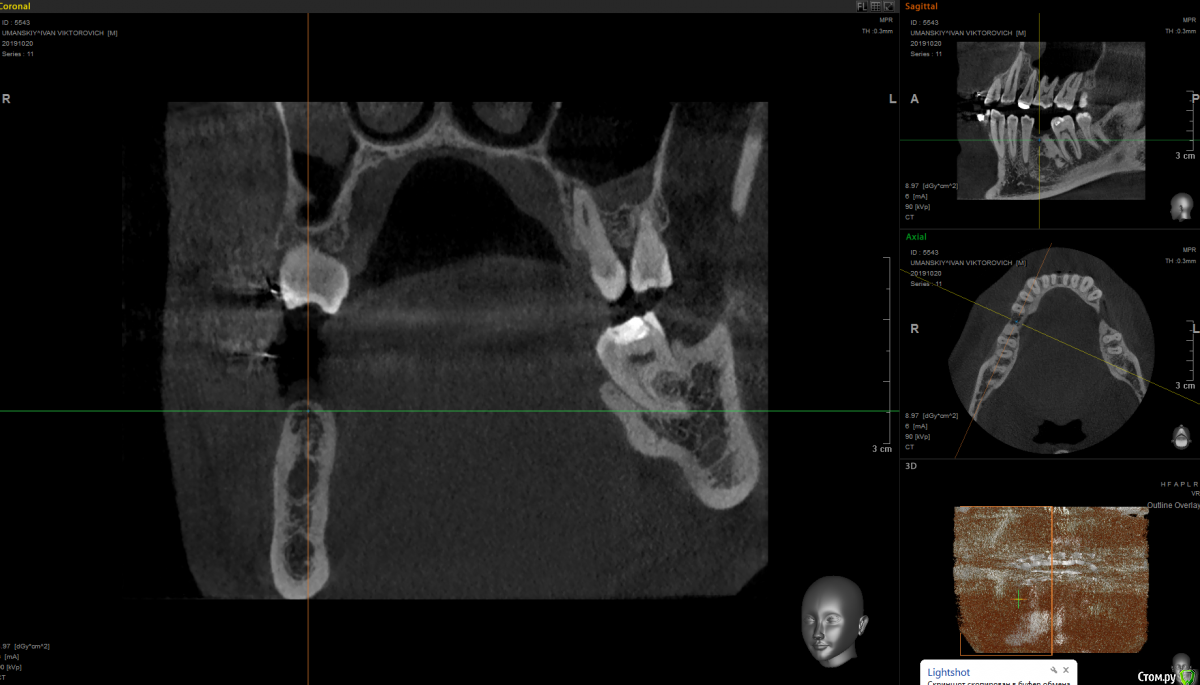

It'sGeorgy Опубликовано 15 января, 2020 Поделиться Опубликовано 15 января, 2020 Здравствуйте!На 2ом прикреплении явно следствие, на 3 и 4 - причина. Вижу 2 варианта развития событий:1: Разрезать, отслоиться. Посмотреть что явилось причиной, удалить причину. Начать готовить ложе под имплантат. 4.0 фрезой провалиться в полость кисты, попытаться извлечь ее через ложе. Поставить имплантат.2: Если через ложе извлечь не удастся, то пойти вестибулярным доступом. Извлечь. Графт, мембрана. 5 мес отдыха. Имплантат. Кто подобным уже занимался, подскажите, насколько перспективен первый вариант? Возможно ли по КТ понять что явилось причиной? На корень не особо похоже. Для остеомы тоже нетипичная картина. Ссылка на комментарий

shy Опубликовано 15 января, 2020 Поделиться Опубликовано 15 января, 2020 (изменено) резидуальная пошел бы через вестибулярный доступ , с графтом или без на усмотрение оперирующего . P.S причину уже удалили до Вас Изменено 15 января, 2020 пользователем shy 1 Ссылка на комментарий